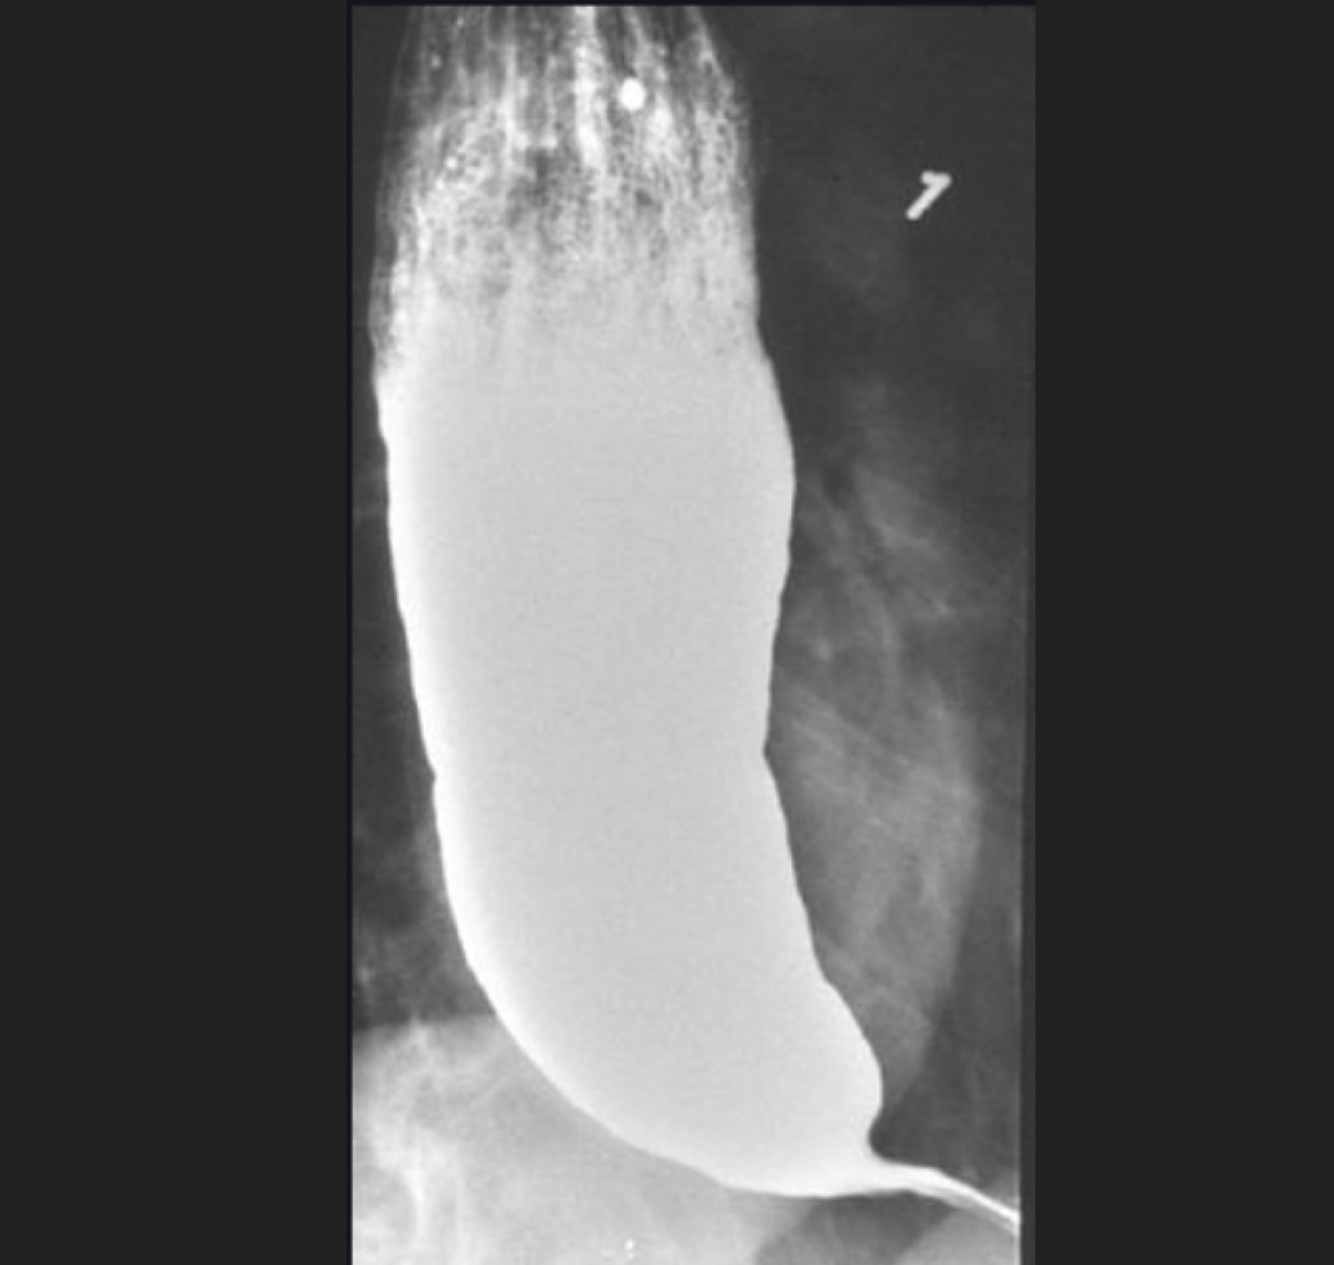

Q

Femenino de 65 años, disfagia, dolor retroesternal

Masculino de 74 años. Sensación de plenitudgástrica, astenia, Adinamia, Hiporexia, pérdida de peso de 16 kg en tres meses